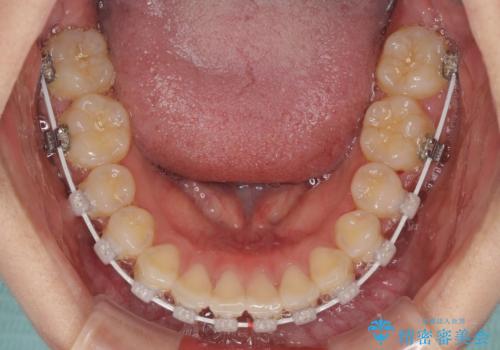

- 上下のデコボコと前歯のクロスバイトを改善したいとのことで来院された患者様です。

極力短期間で治療したいとのことで、ワイヤー装置による矯正治療を行うこととしました。

お住まいが遠方であったため、マウスピースによる矯正治療も提案しましたが、ご自身でのマウスピースの管理の面倒くささと、なるべく早く治療を終えたいとのことで、ワイヤー矯正を選択されました。